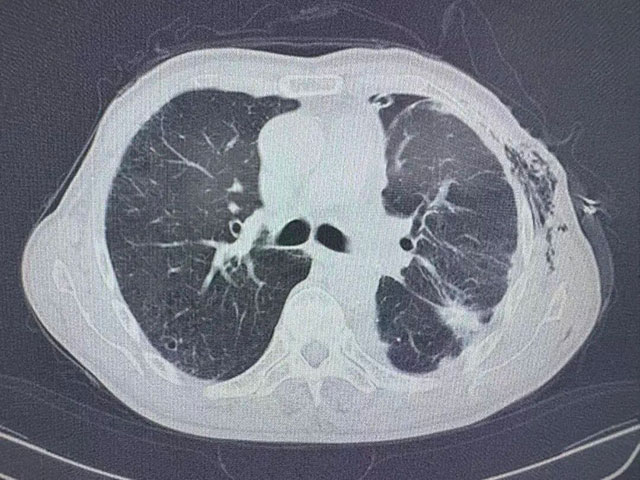

术前胸部CT

入院时,张爷爷的病情已十分危急,胸心外科副主任刘浩副教授检查发现:左肺存在恶性结节,左侧胸腔中量积液,肺部感染严重。

7月9日,刘浩副教授手术团队为张爷爷实施胸腔镜下肺部分切除术+胸腔积液清除术+胸膜活检,成功切除了1.5×1.1×1.0cm大小的浸润性腺癌病灶,并清除了胸腔内积液。术后病理提示,肿瘤已侵犯肺膜,属于晚期肺癌,治疗预后不佳。